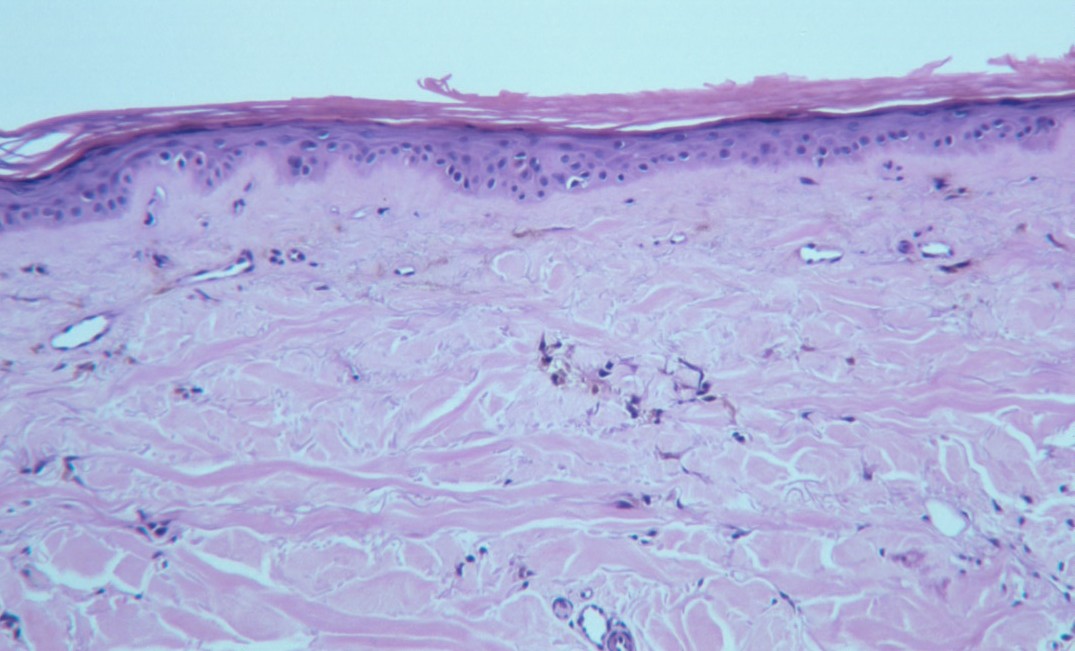

macular-amyloidosis